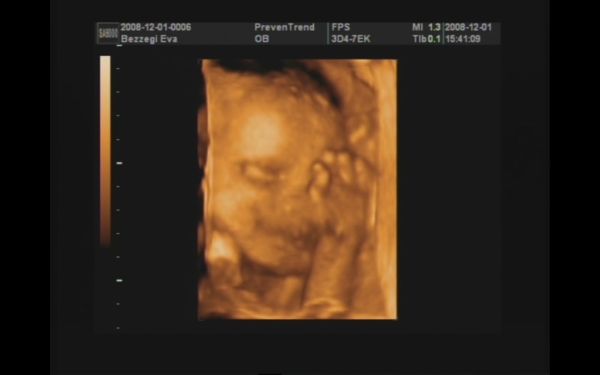

Majd jövök (ha a fiúktól egyszer visszaszerzem a gépet!!), addig is egy pár kép :D! 989 gramm a becsült súlya :shock: , két hete 776 gramm volt!!! Nagyon gyorsan gyarapszik ez a kis pöttömke! :D:D:D

Szerintem kommentálni nem kell :D!! Az integetős, mosolygós kép nekem nagyon tetszik!!